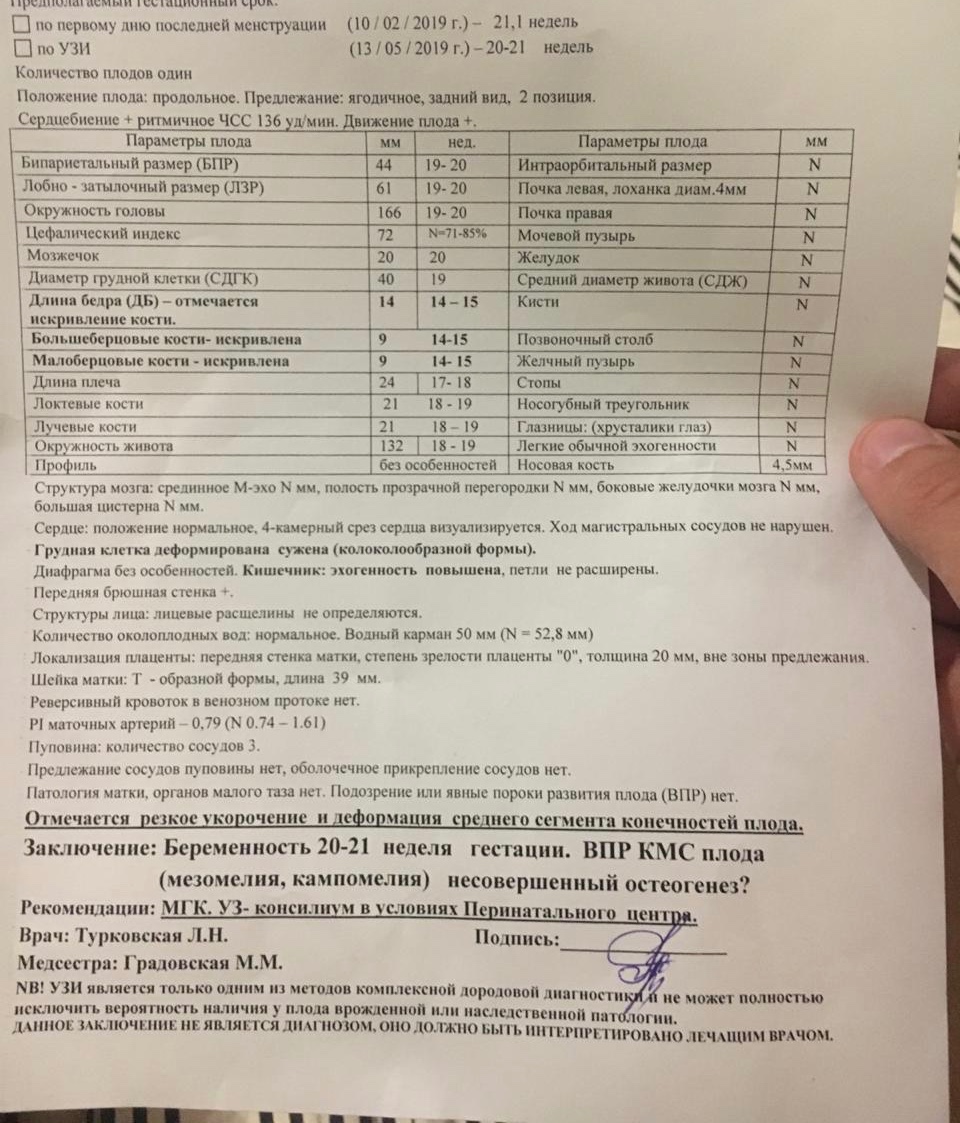

Нормы УЗИ 19-20 недель беременности